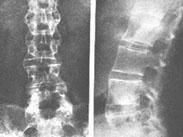

強直性脊柱炎癥狀

• 強直性脊柱炎

628健康網為您分享有關強直性脊柱炎的癥狀,強直性脊柱炎的治療方法,強直性脊柱炎的預防知識,強直性脊柱炎的癥狀圖片,強...